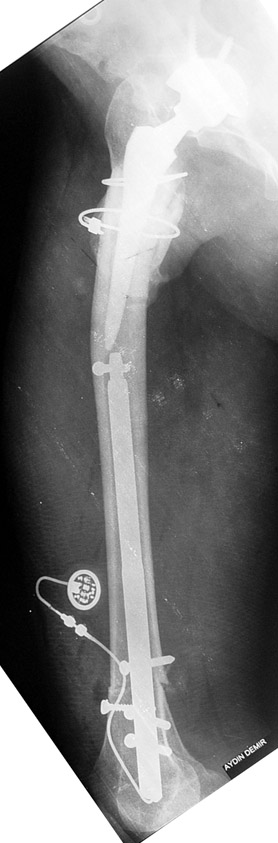

Case 1